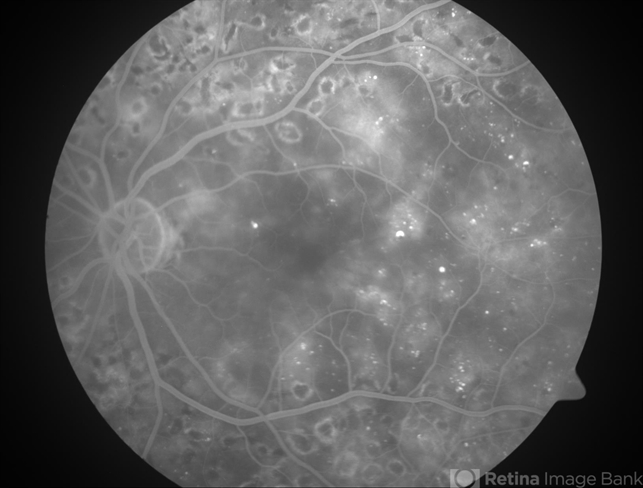

- Diabetic macular edema

- Diabetic macular edema - leaking microaneurysms.